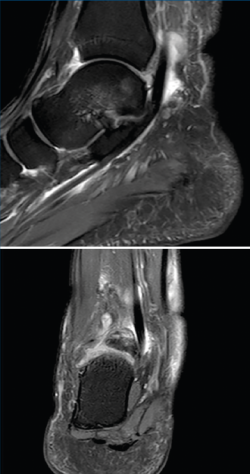

Figura 2. Tenosinovitis del tendón flexor del hallux en resonancia magnética.

Como etiología de dicho dolor se encuentra la afectación ósea (83% de los casos), con el os trigonum (Figura 1) presente en hasta el 8% de la población, la fractura de Shepherd o un tubérculo de Stieda prominente(4). Dentro de la patología de las partes blandas, el flexor largo del hallux (FLH) (Figura 2), en forma de tendinopatía, tenosinovitis estenosante, nódulos, etc., puede originar dolor en el compartimento posterior(5).